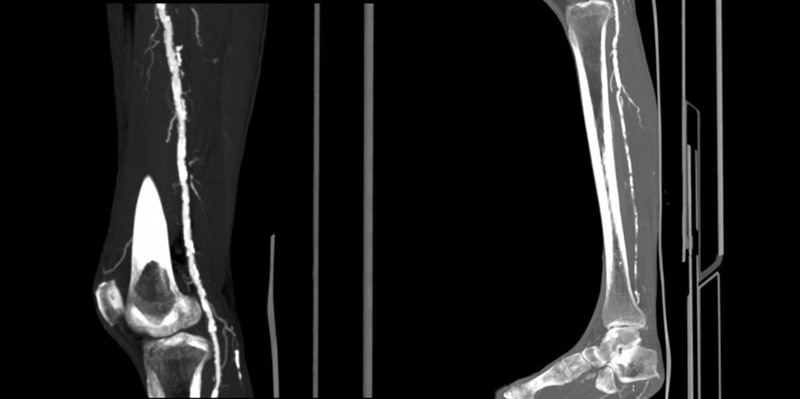

周婆婆慌忙来到重医附二院血管疝腹壁外科求医,住院完善检查后,被查出双侧胭动脉及腘动脉多发管腔中重度狭窄,双侧胫前动脉及左侧胫后动脉节段性闭塞,腹主动脉及分支、双下肢动脉广泛动脉粥样硬化,肠系膜上动脉管腔重度狭窄。手术治疗时,糖尿病足导致的剧烈疼痛使周婆婆配合度差,医生因此仅对其左下肢闭塞动脉进行了球囊扩张。术后,经过系列对症治疗,周婆婆仍觉得下肢疼痛,但她坚持出院。

▲球囊扩张术前下肢动脉CTA/图源 重医附二院疼痛科